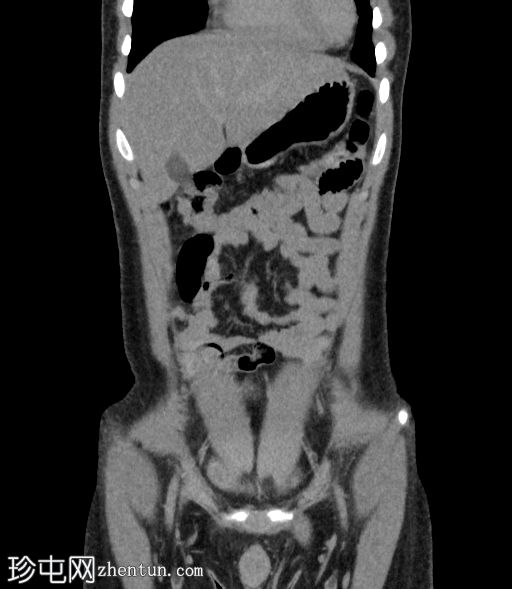

右侧输尿管近端至中段在L3-L5椎体水平向内侧移位

输尿管在L3-L4椎体水平轻度节段性隆起

该段输尿管走行于下腔静脉后方,然后从主动脉和下腔静脉之间向内侧走行,远端转向外侧,正常开口于膀胱输尿管连接处

上中段未显影

远端显影的输尿管走行正常,通向膀胱

右侧输尿管走行异常,属于环腔静脉/腔后输尿管(2型)

影像学上,该畸形可分为两种类型。 1 型是较常见的类型,表现为近端输尿管明显向内侧偏移,呈经典的“S”形或“鱼钩”形,并伴有肾积水。2 型较少见,表现为输尿管袢位置较高,梗阻程度较轻,呈镰刀状。过去主要通过静脉尿路造影进行诊断,而现在 CT 尿路造影和 MR 尿路造影能够更清晰地显示输尿管与下腔静脉的关系以及梗阻程度。